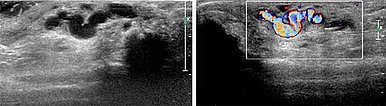

Ultrasound reveals a subcutaneous dilated drainage vein from the digital AVM at the third finger. Color-coded duplex ultrasound (CCDU) confirms the fast-flow arteriovenous shunt with high flow.

Percutaneous ultrasound-guided advancement of the puncture needle into the drainage vein of the digital AVM.